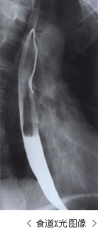

X光检查

食管X光检查是一种利用钡液的摄影法。当服用钡液后,通过判断钡液的移动速度从而观察黏膜状况的检查方式。当黏膜上存有癌细胞等病灶时,其可以将这些微小的凹凸变化以及动态变化以影子的方式呈现出来。是一种判断预测病灶部位及数量的辅助方法。

判断食管癌时,查看胸骨上缘、气管分叉部下缘、横膈膜的范围是很有必要的。X光检查正好能胜任此任务。与内镜检查相比、其虽无法像内镜那样查看病灶的表面情况以及浸润深度、但其却有可确认病灶位置、大小、狭窄度等可方便了解食管总体状态的优点。